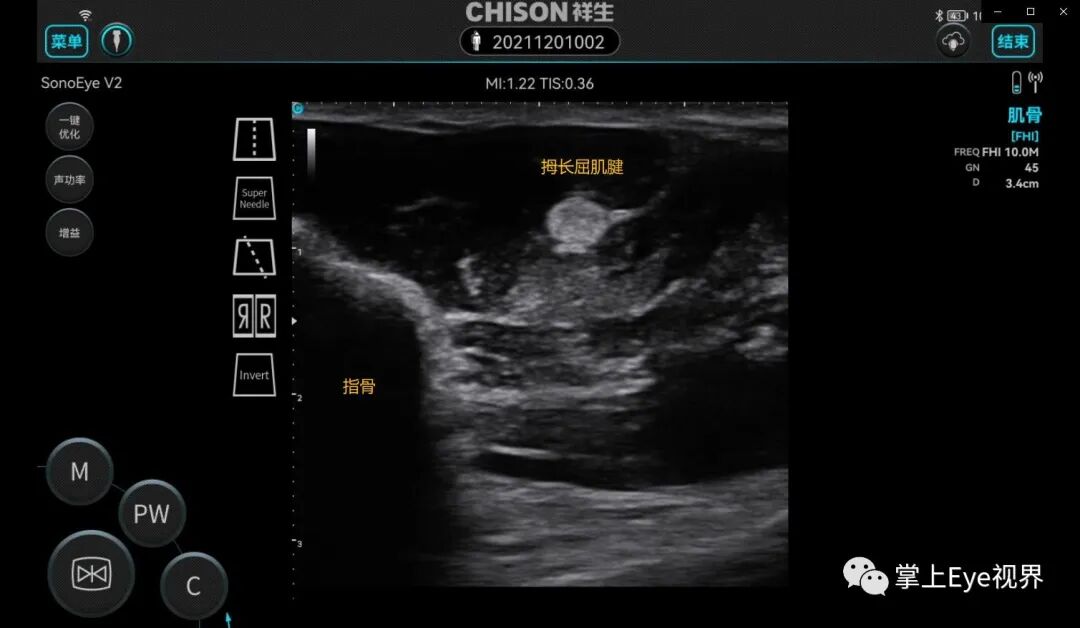

超声波在传播过程中遇到结石-水、气体-软组织等声阻抗差特别大的界面时会发生强反射,因此在界面的后方形成显著的声衰减。常见于骨骼、结石、钙化灶的后方。

彩超伪像是什么超声基础 | 超声伪像_https://www.jmylbn.com_新闻资讯_第3张

图为拇长屈肌腱声像图